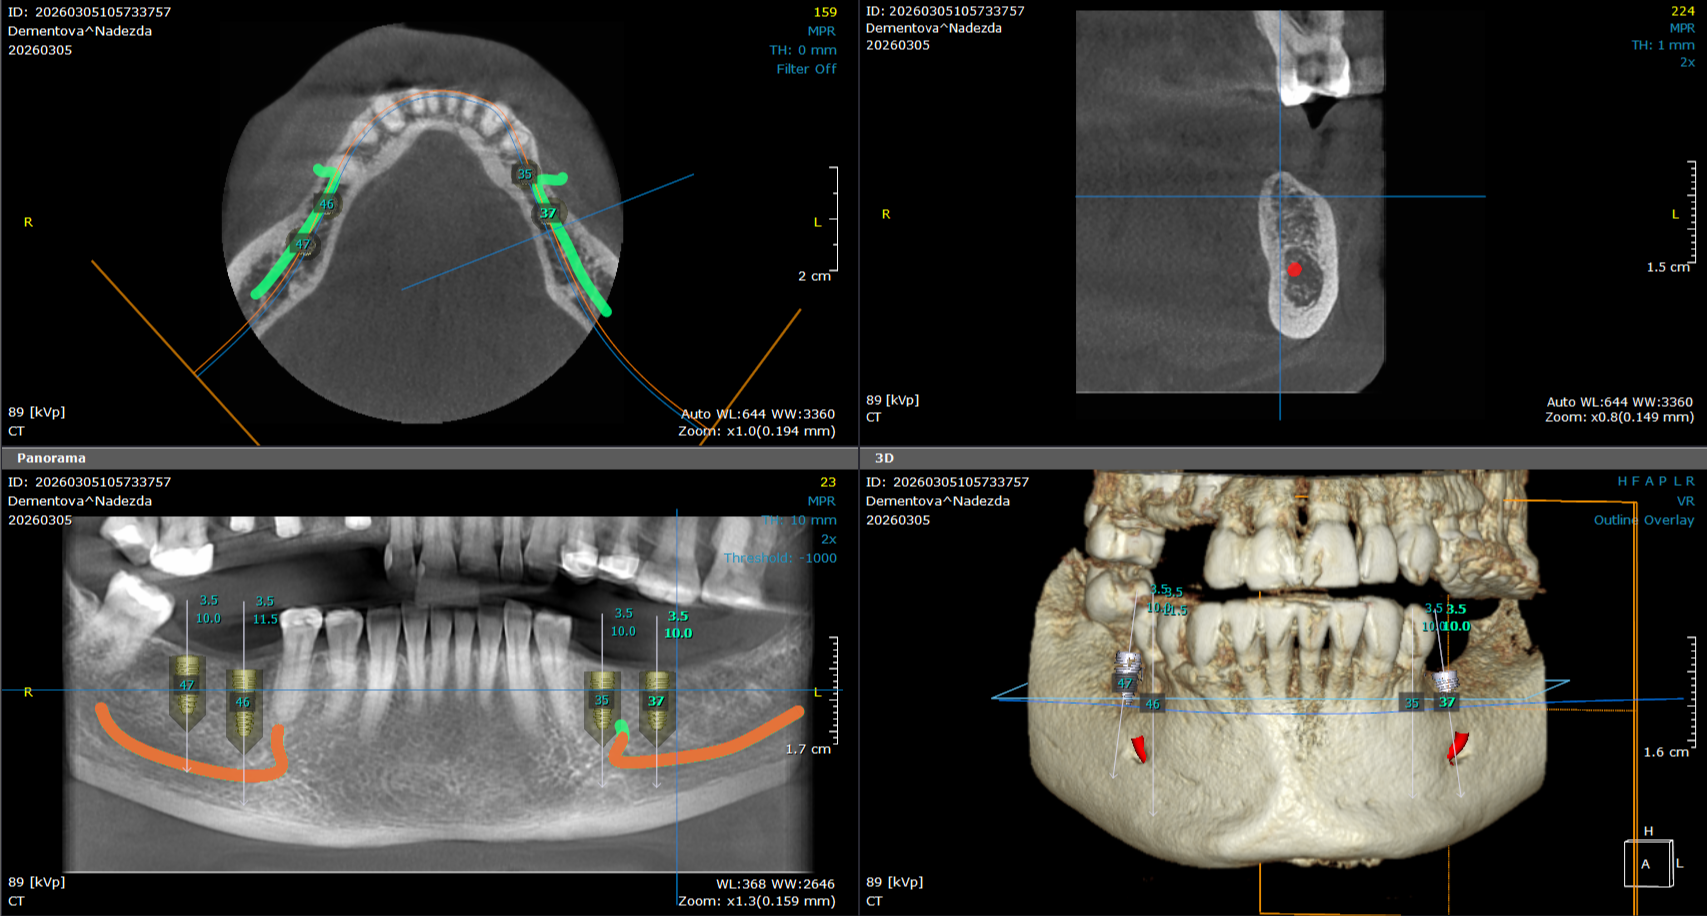

3D snimanje zuba predstavlja savremenu dijagnostičku metodu u stomatologiji koja omogućava trodimenzionalni prikaz zuba, vilice i okolnih anatomskih struktura. Ova tehnologija, poznata kao CBCT (Cone Beam Computed Tomography), pruža izuzetno precizne informacije koje stomatolozima pomažu u planiranju terapije i izvođenju složenih stomatoloških procedura.

Za razliku od klasičnih 2D snimaka, 3D snimci omogućavaju detaljan prikaz kosti, položaja zuba, nervnih kanala i sinusa, što je posebno važno kod planiranja ugradnje implantata, ortodontske terapije, endodontskog lečenja i hirurških intervencija.

3D snimanje omogućava preciznu procenu količine i kvaliteta kosti, kao i tačno određivanje pozicije implantata.

3D snimanje zuba posebno je važno kod planiranja dentalnih implantata, ortodontske terapije, procene impaktiranih umnjaka i dijagnostike različitih promena u kosti. Snimanje je brzo, bezbolno i traje svega nekoliko sekundi.